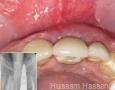

2 Months

7 Months